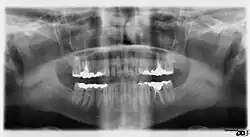

- Контроль этапов лечения и динамики течения заболеваний (качество пломбировки канала, штифты, имплантаты и пр.).